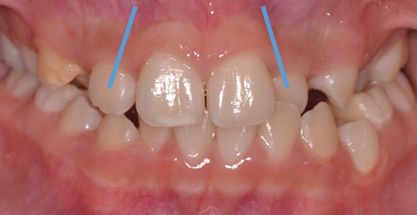

Dental impactions may occur for several reasons. A common occurrence is insufficient arch length leading to crowding. Another potential reason is early loss of primary teeth without proper space maintenance, allowing the permanent dentition to drift mesially and block out the primary tooth's successor. Maxillary canines are the most commonly impacted teeth besides third molars. These teeth have the longest path of eruption, are one of the last teeth to erupt into the mouth, easily become blocked out due to crowding or trauma history, and have a genetic component to being palatally impacted.5,6 Early signs of canine impaction may be severe crowding and the permanent lateral incisor crowns flaring distally. The crown of the impacted canine, in essence, is applying pressure to the roots of the lateral incisors in these instances (Figure 3 and Figure 4).

Fig 3. Impacted canine, dentofacial signs.

Figure 3

Fig 4. Impacted canine, radiographic signs. Lateral incisor crown distal flaring is apparent.

Figure 4